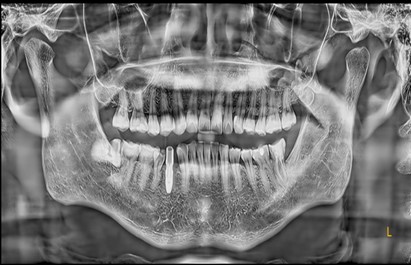

Preoperative Images

May 4, 2025: Extraction of the affected tooth.

Immediate implant placement (first-stage surgery) was performed right after tooth extraction.